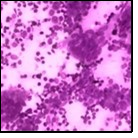

Fine needle aspiration can demonstrate a cellular exudate indicative of an abscess with an intense inflammatory infiltrate preponderantly composed of neutrophils. Ductal epithelial cells may be absent. Cytological examination delineates abundant and accumulated epitheloid histiocytes, neutrophils, lymphocytes with a variable degree of granuloma formation and an absence of necrosis 5.

Figure 10.Granulomatous mastitis with a ductal circumscription of epitheloid cells, plasma cells, lymphocytes and neutrophils 18.